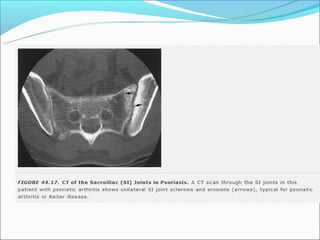

B27- SACROILEÍTE

EA e DII: Simétrica e bilateral

No início erosiva e progride para esclerose e fusão.

Sacroileíte

S. Reiter ou A. Psoriática

podem exibir

comprometimento uni

ou bilateral (50%)

Quando bilateral

freqüentemente

assimétrica.